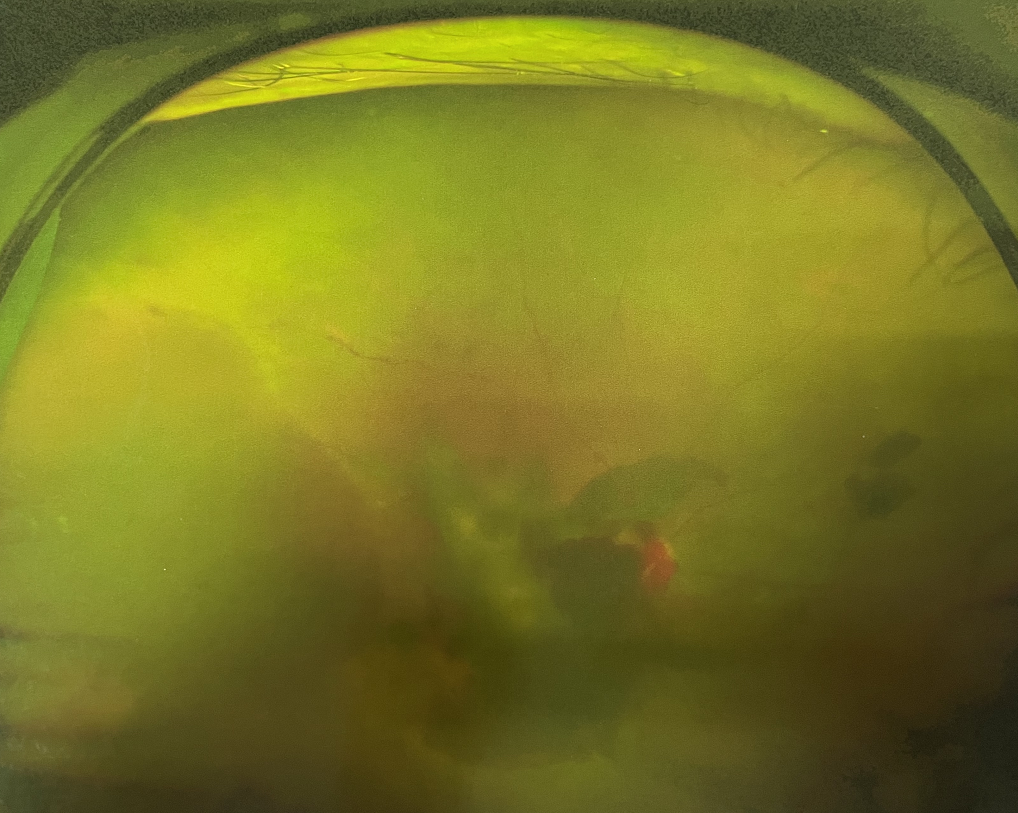

眼底出血是指眼內(nèi)視網(wǎng)膜出血,或玻璃體內(nèi)出血。眼底位于眼睛深處,所以這類出血只靠肉眼是看不到的,早期可能不紅、不痛、不癢,需通過專業(yè)的眼底檢查才可看到,往往短期內(nèi)就可造成視力驟降甚至失明!

同樣的,眼底出血也是一種癥狀,而非病種。誘發(fā)眼底出血的原因很多,常見的有全身性血管病和血液病、視網(wǎng)膜血管異常、機(jī)械性阻塞、炎癥性疾病或免疫復(fù)合物侵犯血管壁等。

一只眼睛眼底出血是怎么回事?眼底出血的高發(fā)人群有哪些?

1、高血壓患者

2、糖尿病患者

3、老年性黃斑變性患者

4、高度近視患者(近視>600度)

眼底出血是較為嚴(yán)重的眼疾,治療不及時會有失明的風(fēng)險。一旦眼睛出現(xiàn)視力下降、視物變形、視野缺損或眼前有黑影等視覺異常的情況,應(yīng)及時到醫(yī)院進(jìn)行眼底檢查,早發(fā)現(xiàn)、早治療,以免貽誤病情。